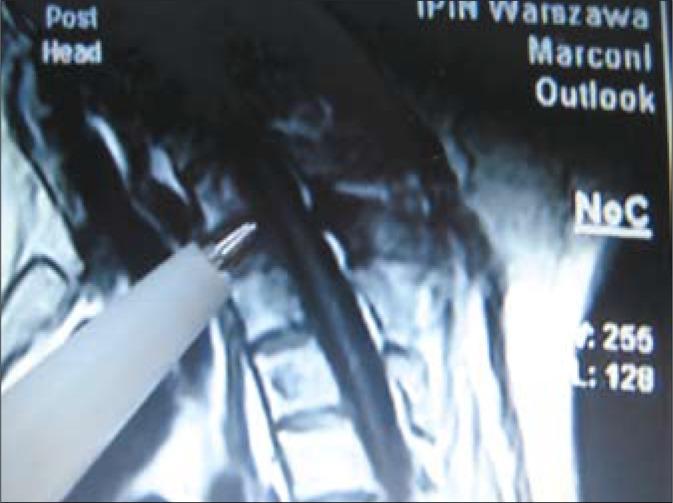

Prostate cancer (PCa) is a major health problem and one of the main causes of cancer mortality in men [1]. In patients with PCa, bone metastases manifest in 100% of patients when the PSA level exceeds 100 ng/ml causing pains and posing a risk for pathological fractures [2]. We report a case of a 70-year-old male with PCa and pathological fractures of the vertebrae, in whom we observed long-term regression and an 8-year-survival while undergoing continuous therapy. As far as we know, this is the first reported case in literature with such an unexpected outcome.